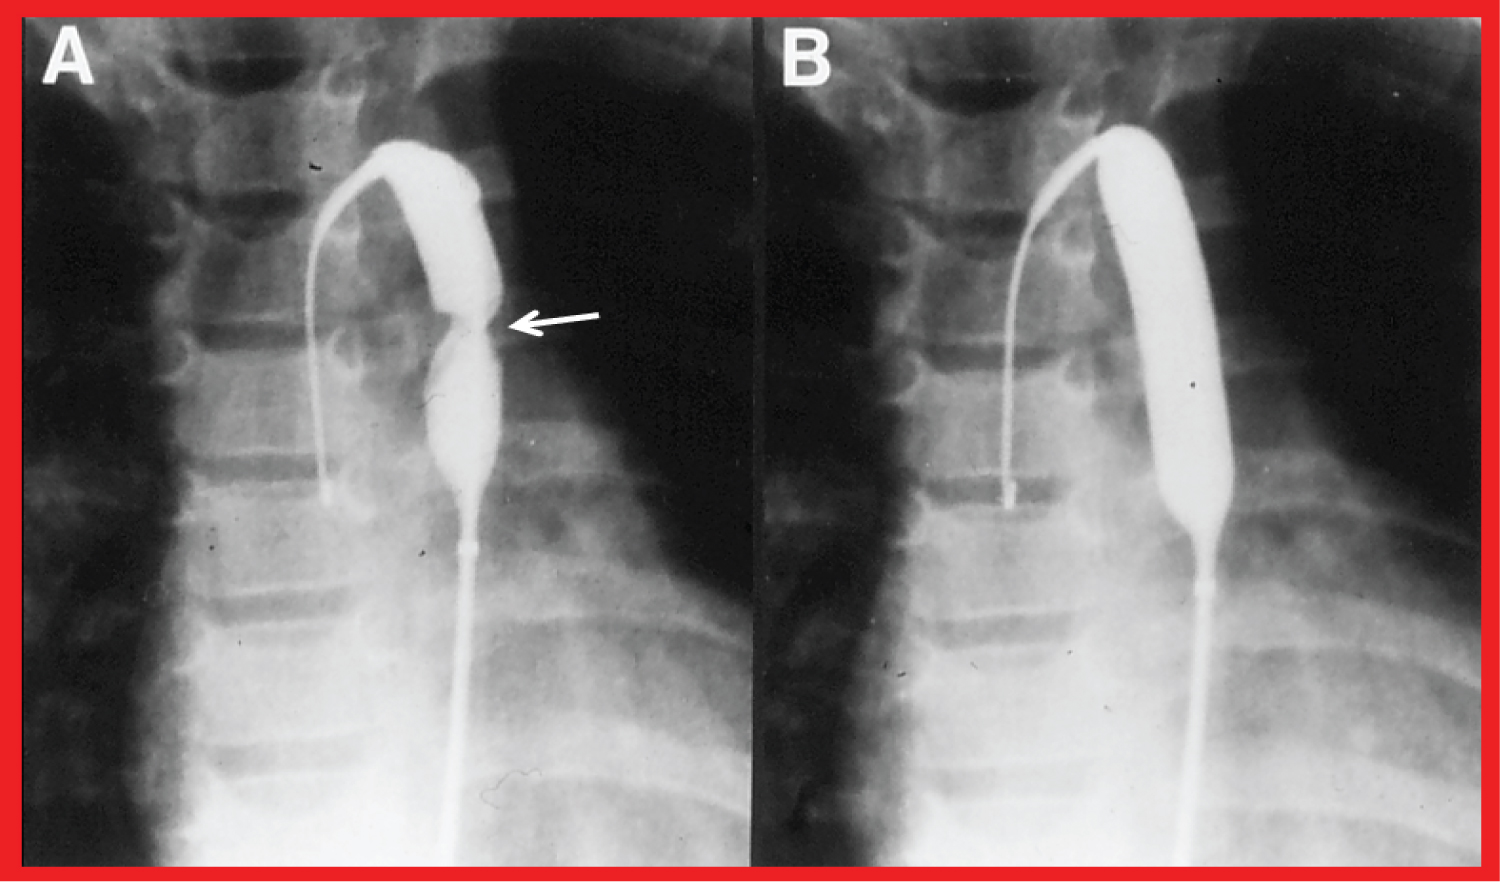

At first the pathologic features of coarctation of the aorta (CoA) were reviewed. Then, a description of historical aspects [7-9], indications [72-75], and the procedure of balloon angioplasty (Figure 8) ensued [73-75].

Figure 8: Selected cineflurograpic frames in postero-anterior projection in a child, demonstrating an angioplasty balloon across the aortic coarctation with A) Waisting (arrow) of the balloon during the initial phases of balloon inflation; B) The waist has completely disappeared; with further balloon inflation. The guide wire (GW) is positioned in the ascending aorta (AAo) [73]. View Figure 8